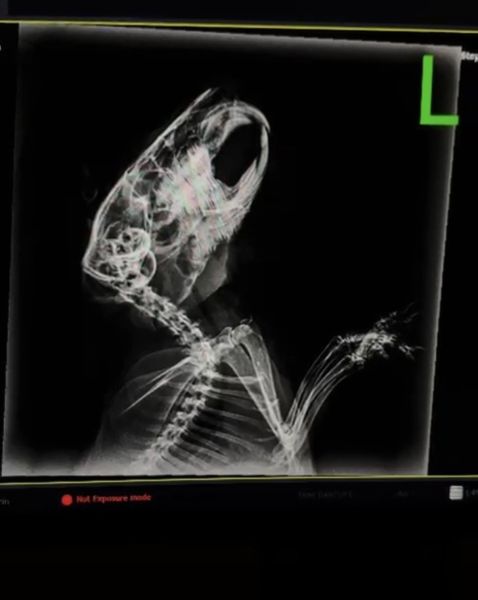

I have a Guinea Pig called Anakin. She presented with weight loss, wonky teeth and a large weeping mass on her jaw last November. Since then, she has been on antibiotics for about a week initally, then saw a Small Animal Vet who performed a teeth burring, xrays and potential abcess drainage. However, the Xrays showed no abcess or tumor so they just burred down her teeth and sent over the xray pics. Unfortunatley a few days after the lump was still weeping, so we took her back to the vet and they prescribed baytril. Upon monitoring her up until now from that point, her teeth are back to being diagonal and the lump is hard and unmoving, still with pus. We are kind of at a loss. She has already been under anasthesia once, and we are not sure if it's fair to do it again. She is stable with her weight, but only at 0.61kg. Any advice is appreciated.

X-Ray pics below: